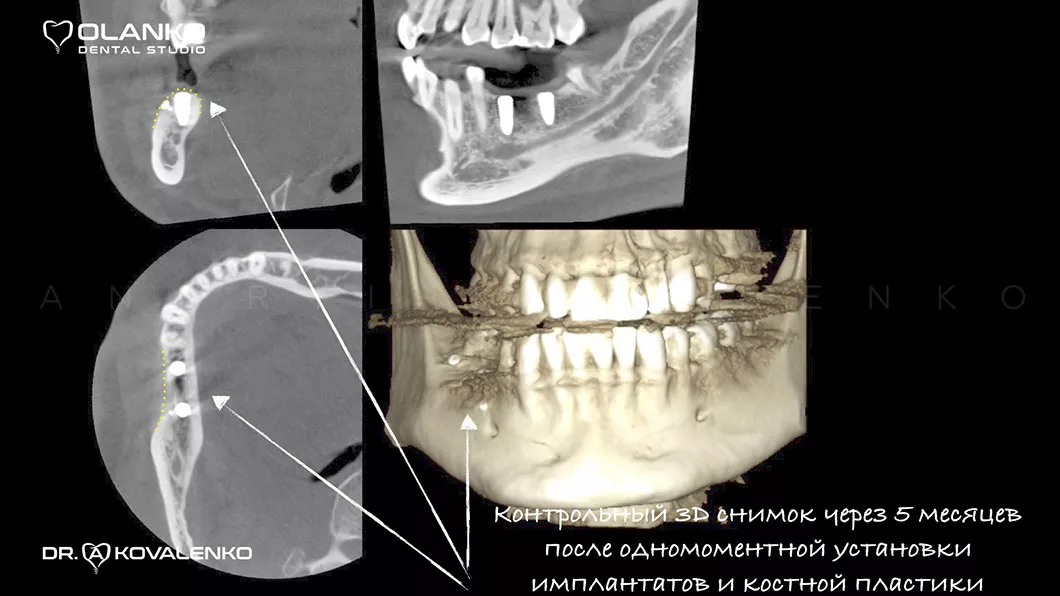

Специалисты Olanko dental studio (Оланко) г. Бровары, при выборе метода костной пластики, проводят детальный анализ компьютерной томографии и виртуально расставляют положение будущих имплантатов в специальном программном обеспечении IMPLANT STUDIO 3Shape.